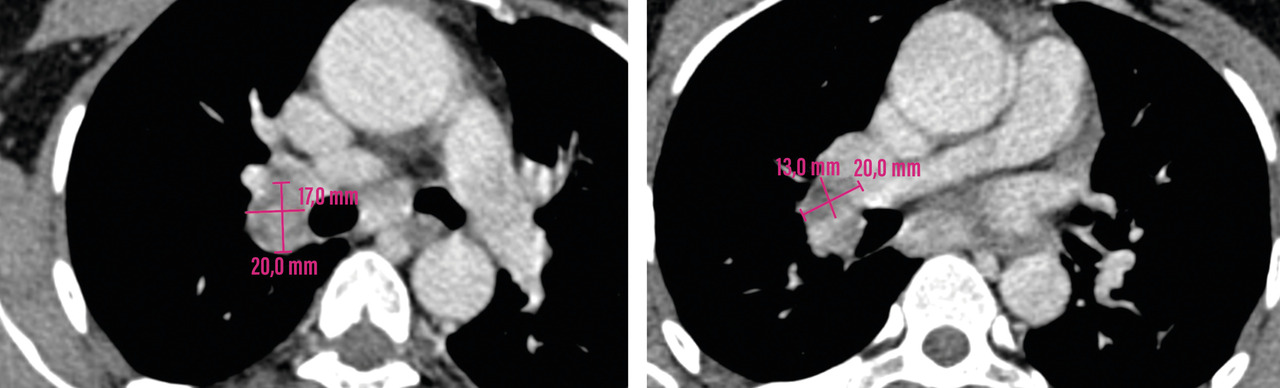

Un scanner cervico-thoraco-abdomino-pelvien est réalisé, à la recherche de signes radiologiques d’une pathologie associée. Il montre des adénopathies médiastino-hilaires droites, nécrotiques (fig. 2) et un foyer de micronodules parenchymateux pulmonaires lobaires inférieurs droits, confluents, avec un nodule central, réalisant le signe de la galaxie, visible sur une tomodensitométrie axiale du thorax (fig. 3). Ces signes sont-ils ceux d’une sarcoïdose pulmonaire active ou d’une atteinte granulomateuse de type tuberculose ou d’une autre cause ?